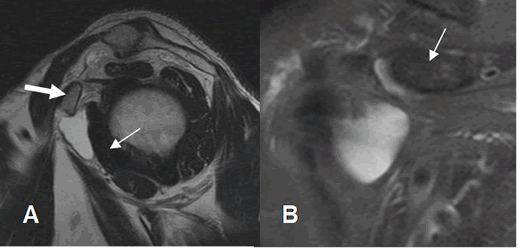

Fig 145. Bursitis subcoracoidea.

A: RM sagital en T2. Colección líquida por delante del músculo subescapular (Flecha delgada) y por debajo de la coracoides (Flecha gruesa), que corresponde a bursitis subcoracoidea.

B: RM coronal en STIR. Colección líquida por debajo de la coracoides (Flecha delgada), que corresponde a bursitis subcoracoidea.